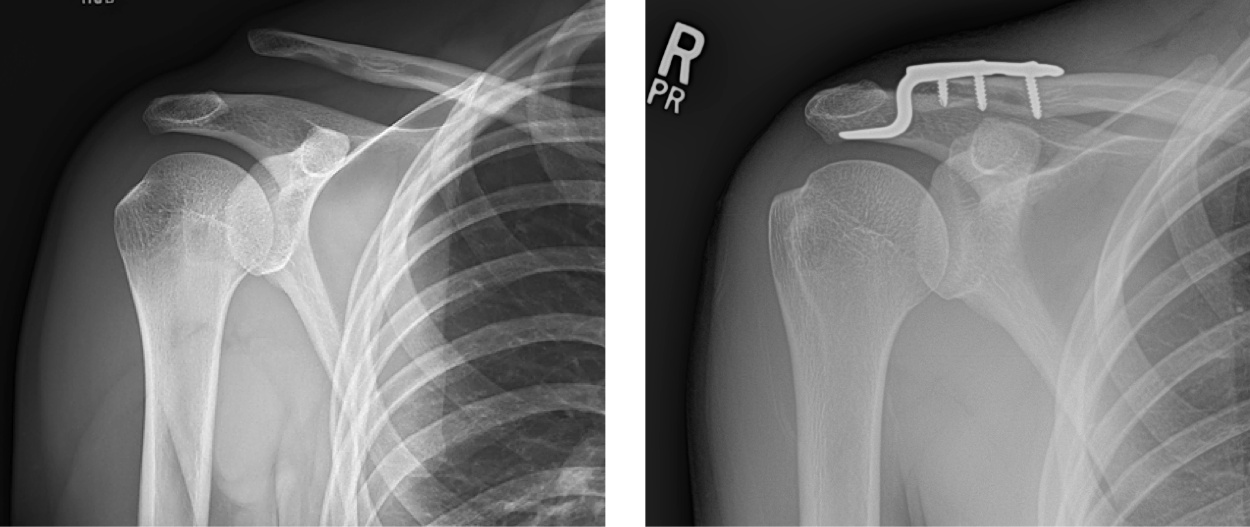

There are ligaments between the end of the clavicle and the shoulder blade to keep the clavicle close to the body. These ligaments can be injured, usually from a direct fall onto the shoulder, causing the end of the clavicle to stick up. This is a shoulder separation or acromio-clavicular joint injury. It can usually be treated without surgery; however, if there is persistent pain or very high grade separations, surgical repair can be performed.

Pre-operative and post-surgical radiographs of a patient who sustained a high grade AC joint separation, treated acutely with a hook plate.